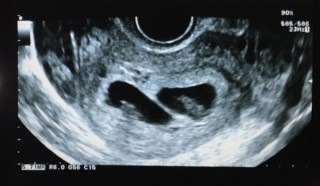

二卵性の双子です。先週心拍が確認できましたが、その時はただの丸だったのに、今は長くなって2つとも1.3㎜ほど。もうすぐ胎芽から胎児に。まだまだ不安は尽きないけれど、成長が楽しみです。